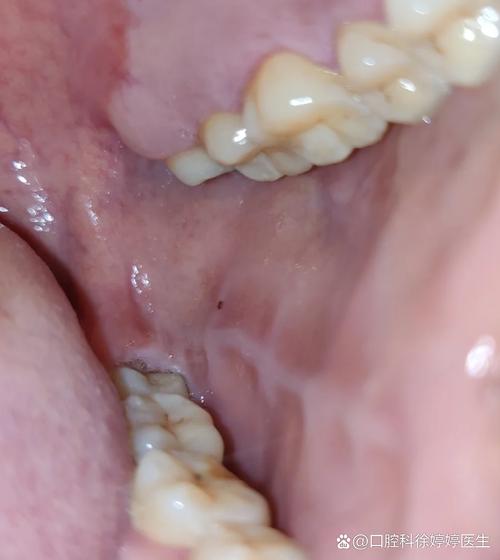

口腔内侧突然鼓包是何原因?

粘液腺囊肿(Mucocele)- 最常见

- 成因: 这是最常见的原因,通常是口腔内的小唾液腺导管被咬伤或堵塞,导致唾液无法正常排出,积聚在腺体或周围组织中形成的。

- 外观: 半透明、柔软、有弹性,像一颗水泡或一颗装了液体的“小气球”。

- 颜色: 可能是浅蓝色、粉红色或正常的口腔黏膜色。

- 位置: 最常见于下唇内侧,但也可能出现在舌腹、颊黏膜等部位。

- 感觉: 通常不痛,除非不小心咬破。

- 变化: 大小可能会在短时间内发生变化,有时会自行破裂,流出一些黏稠液体,然后又慢慢长大。